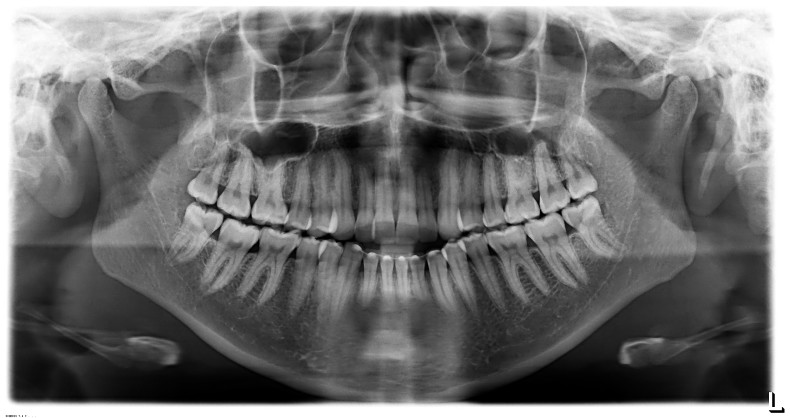

Der extraorale Befund (Abb. 1a–c) ergab ein gerades Durchschnittsgesicht mit leicht vergrößertem Nasolabialwinkel, ein symmetrisches Gesicht bei potenziell inkompetentem Lippenschluss sowie einen dolichofazialen Gesichtstyp. Intraoral lag beidseits annähernd eine Angle-Klasse I mit frontal offenem Biss (–2,5 mm) sowie ein dental-transversal zu schmaler Oberkiefer vor, woraus ein Kopfbiss von 13 und 23 resultierte. Des Weiteren zeigten sich ein persistierendes viszerales Schluckmuster und eine Inkongruenz der Kiefermitten (Abb. 2a–e; Abb. 3).